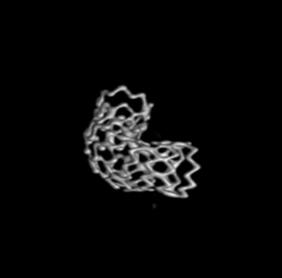

- WILLIS® 4.0×10mm。

3D重建图示支架贴壁良好。

- 载瘤动脉位于海绵窦前膝部,内径较均匀,无分支血管,但有一定弯度,如使用覆膜支架,释放难度高,有贴壁不全风险。但覆膜支架可以重建血管壁,完全治愈动脉瘤。

- 综合考虑并结合自己丰富的临床经验,术者决定克服困难,使用WILLIS®覆膜支架进行手术。故术中选用4.5×16mm WILLIS®覆膜支架,以期治愈动脉瘤。